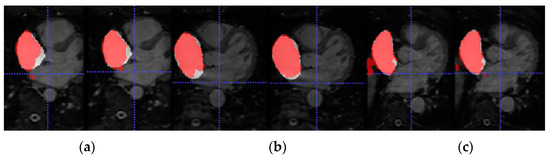

To further assess the evaluation performance of each model, qualitative results of the segmentation predictions were obtained.

Figure 5 shows the axial view of predictions obtained for three representative patients (and slices) of the testing cohort from Database 3 with the different trained models for LA segmentation.

Due to the absence of previous works that employ Database 3 solely as an external validation dataset, we are not able to compare the generalization ability of our proposed model. On the other hand, a visual representation of the increased performance of the models with SDA can be seen in Figure 5 and Figure 6 for LA and RA segmentation tasks, respectively. As we can observe, the blood pool prediction segmentation of the LA and RA performs best in the SDA model.

Figure 5. From top to bottom, axial slice of LA segmentations for three patients obtained through models (a) LGE-MRI, (b) w/o SDA and (c) w-SDA. Ground-truth mask in white, prediction mask in red and intersection in pink.